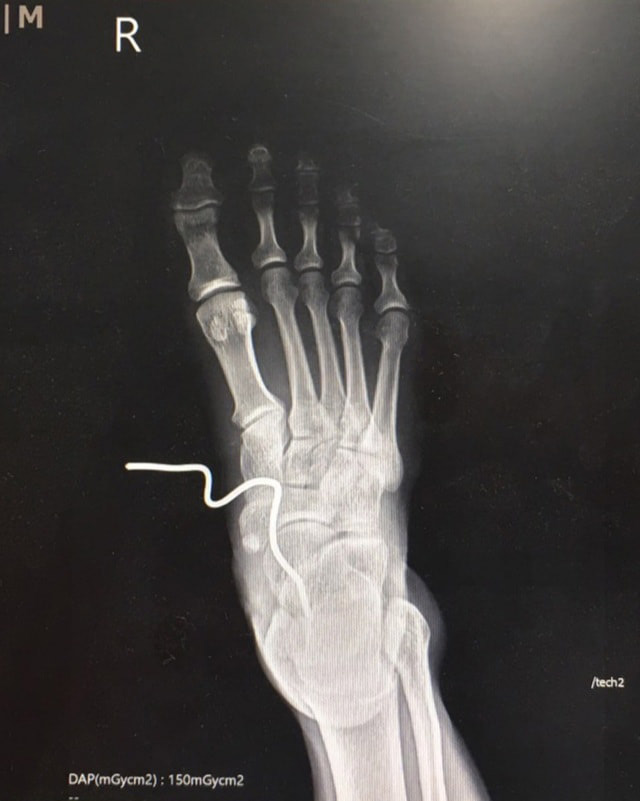

เริ่มเจ็บปวดมากขึ้น ลองจับจะดึงออกด้วยตนเอง ก็ไม่สามารถทนความเจ็บปวดได้ ขยับข้อเท้าแทบไม่ได้ จึงรีบให้ญาติขับรถมาส่งโรงพยาบาลสิชล เมื่อเข้าห้องฉุกเฉินทีมได้เข้ามาดูอาการทันที ให้ยาระงับปวด ส่งเอกซเรย์จะพบว่าเหล็กแทงลึกเข้าไปกว่า 2 นิ้ว จนถึงกระดูก รีบปรึกษาแพทย์ผู้เชี่ยวชาญด้านกระดูก เตรียมผู้ป่วยเข้าห้องผ่าตัด งดน้ำ อาหาร ให้น้ำเกลือ ฉีดยาป้องกันบาดทะยัก ยาต้านเชื้อ ป้องกันการติดเชื้อตามมาภายหลัง เพราะเป็นบาดแผลปนเปื้อนสกปรกจากเหล็กที่ฝังดิน มีสนิมเกรอะ

การผ่าตัดจะดึงเหล็กออกแล้วปิดแผลไม่ได้

ต้องเปิดปากแผลให้กว้าง ล้างทำความสะอาด เพื่อเอาเศษผงดิน สนิมเหล็กออกให้หมด พบว่ากระดูกแตกด้วย เอ็นฉีกขาด

คงต้องให้ยาต้านเชื้อเข้าเส้นอีกหลายวัน

เพื่อป้องกันไม่ให้ติดเชื้อในกระดูก